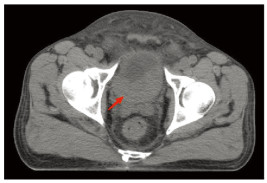

2017年12月20日患者血清肌酐开始升高,随后病情迅速进展,并发肾积水、梗阻性肾功能衰竭及尿路感染,通过输血、抗感染及血液透析治疗后缓解。考虑到生活质量,患者拒绝膀胱根治性手术切除。2018年1月9日开始实施放射治疗。放疗计划:GTV1(瘤床):64 Gy/32 Fr,CTV1(膀胱外放2 cm):54 Gy/27 Fr,CTV2(淋巴结引流区):50 Gy/25 Fr。当照射剂量达到24 Gy/12 Fr时,患者的血清肌酐恢复正常。血清肌酐(Scr)的变化趋势见图 3。患者在2018年2月21日结束放疗,此时腹部MRI检查提示膀胱内仍有残留肿瘤。2018年3月9日开始行吉西他滨+洛铂(吉西他滨1.7 g,d1、8+洛铂50 mg)化疗一个疗程,此后患者因化疗后骨髓抑制终止化疗。考虑仍有肿瘤残留,建议重启化疗,但患者拒绝化疗,患者自行口服两个疗程阿帕替尼。2018年6月8日复查盆腔磁共振提示肿瘤仍有部分残留,于2018年7月9日、2018年8月3日、2018年8月24日、2018年9月24日、2018年10月15日和2018年11月28日给予吉西他滨(1.6 g,d1、8)治疗六个疗程。治疗结束后患者残留病灶基本消退。此后患者3个月规律复查一次。由于患者治疗后无尿路症状不适,因此患者拒绝膀胱镜检查,只接受无创的腹部CT增强及尿脱落细胞学检查。最近一次于2022年12月13日复查腹部增强CT及尿脱落细胞学检查,提示未见肿瘤复发及转移,见图 4。随访至今患者无病生存期超过5年。

| 图 4 2022年12月13日CT扫描结果 Figure 4 CT scan results on December 13, 2022 |